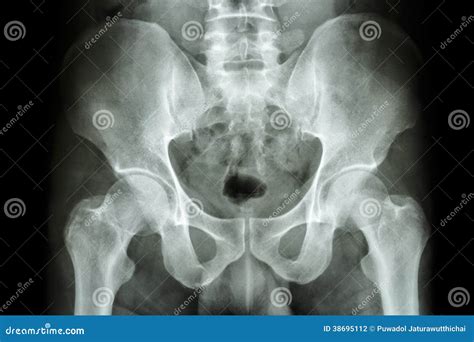

Interpreting a Normal Hip X Ray

Interpreting a Normal Hip X Ray involves evaluating the images for various features and abnormalities. Key aspects that radiologists look for include:

• The alignment and position of the femoral head within the acetabulum.

• The presence of fractures, dislocations, or other bony abnormalities.

• The condition of the joint space, which can indicate the presence of osteoarthritis or other degenerative changes.

• The presence of any soft tissue swelling, calcifications, or other abnormalities.

Radiologists use specific terminology and measurements to describe the findings on a Normal Hip X Ray. Some common terms and measurements include:

Term/Measurement Description

Acetabular Index Angle between the acetabular roof and the horizontal plane, used to assess hip dysplasia.

Center-Edge Angle Angle between the vertical line through the center of the femoral head and a line from the center to the lateral edge of the acetabulum, used to assess hip coverage.

Shenton’s Line A smooth curve formed by the inferior border of the superior pubic ramus and the inferior border of the femoral neck, used to assess hip dislocation.

Common Findings on a Normal Hip X Ray

A Normal Hip X Ray can reveal a variety of findings, ranging from normal anatomy to significant abnormalities. Some common findings include:

• Normal hip anatomy, with well-aligned bones and joints.

• Fractures of the femoral neck, intertrochanteric region, or acetabulum.

• Hip dislocations, which can be anterior, posterior, or central.

• Osteoarthritis, characterized by joint space narrowing, osteophyte formation, and subchondral sclerosis.

• Hip dysplasia, with a shallow acetabulum and abnormal femoral head coverage.

• Avascular necrosis, which can appear as areas of bone density changes and collapse.